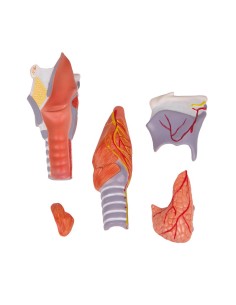

3B Scientifique, modèle anatomique du larynx, deux fois agrandi, en 7 parties G21